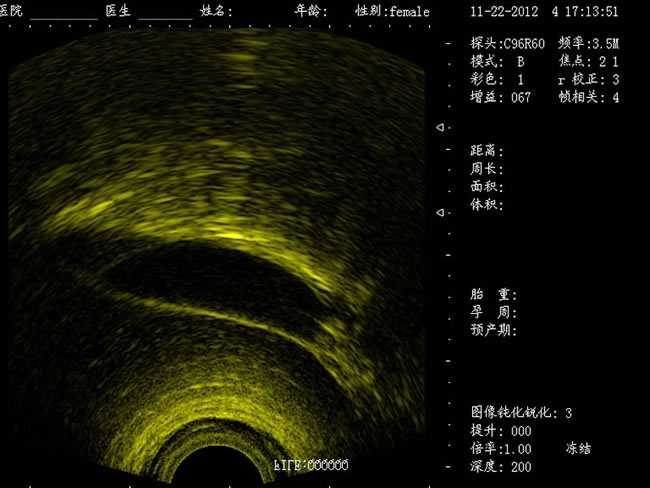

DW-400

功能特點:

定位精確 手術效率高:實時動態頻率掃描等全數字超聲成像技術、生成精確的圖像引導手術器械迅速到大手術位置,避免損傷子宮內膜和子宮穿孔的現象,即減輕了患者的痛苦又極大提高了手術效率。

高密度全數字波束形成:采用全新一代混頻技術、數字嵌入系統及數字整序技術

有效提升系統的穩定性、可靠性:實時動態孔徑成像,充分保證圖像的精度和清晰度

標準配置:

主機

CXA10R/6.5MHz 腔內探頭

12.1英寸LED液晶顯示器

擴陰器

選配:CXA60R/3.5MHz 凸陣探頭

隨著醫療技術水平的提高,目前婦產科手術中所應用的相關設備也有了加大的改進。尤其是在人工流產手術中,將B超婦產科手術監視儀應用到手術過程中,彌補傳統手術中所采用設備的不足之處,減輕手術中患者的疼痛感覺,使得手術順利的完成。這種儀器相比于傳統的儀器來說,其在操作上更為方便和簡單,能夠對妊娠反應有很好的療效。